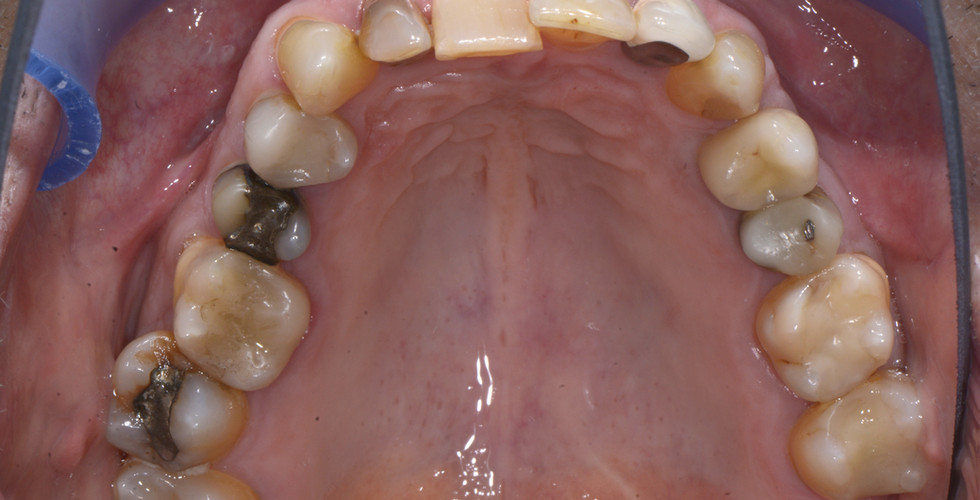

Vorher-Nachher Beispiele aus der Praxis